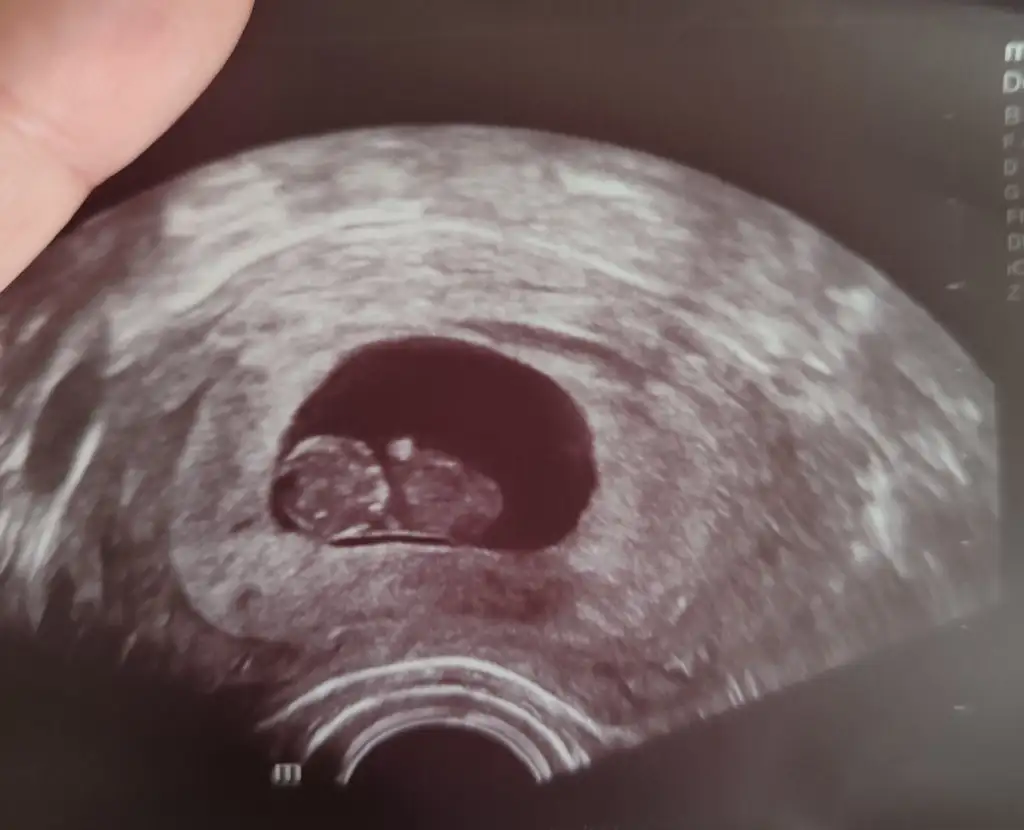

Milletin ne dediğine umursama canım, bebeğineGittim canım. Ben de size yazacaktım ilaçların son durumunu. Bebiş çok şükür iyi, tosbalak olmuş bayayan yatıyordu, soldaki başı, sağdaki gövdesi doktor bir hafta daha fitili sadece akşamladı kullan ve bırak dedi. 12. Haftada fetal DNA testi istediğimi söyledim. 12. Haftaya koydu bir dahaki muayeneyi. Sanırım o hafta fetal DNA testimiz de olur.

Ama tosbalağıma bakın kızlar kocaman olmuş 9+3 olmuşuz. Uygulamayla aynı gidiyor. 26mm.aydodo yarın da senden güzel haberi bekliyoruz